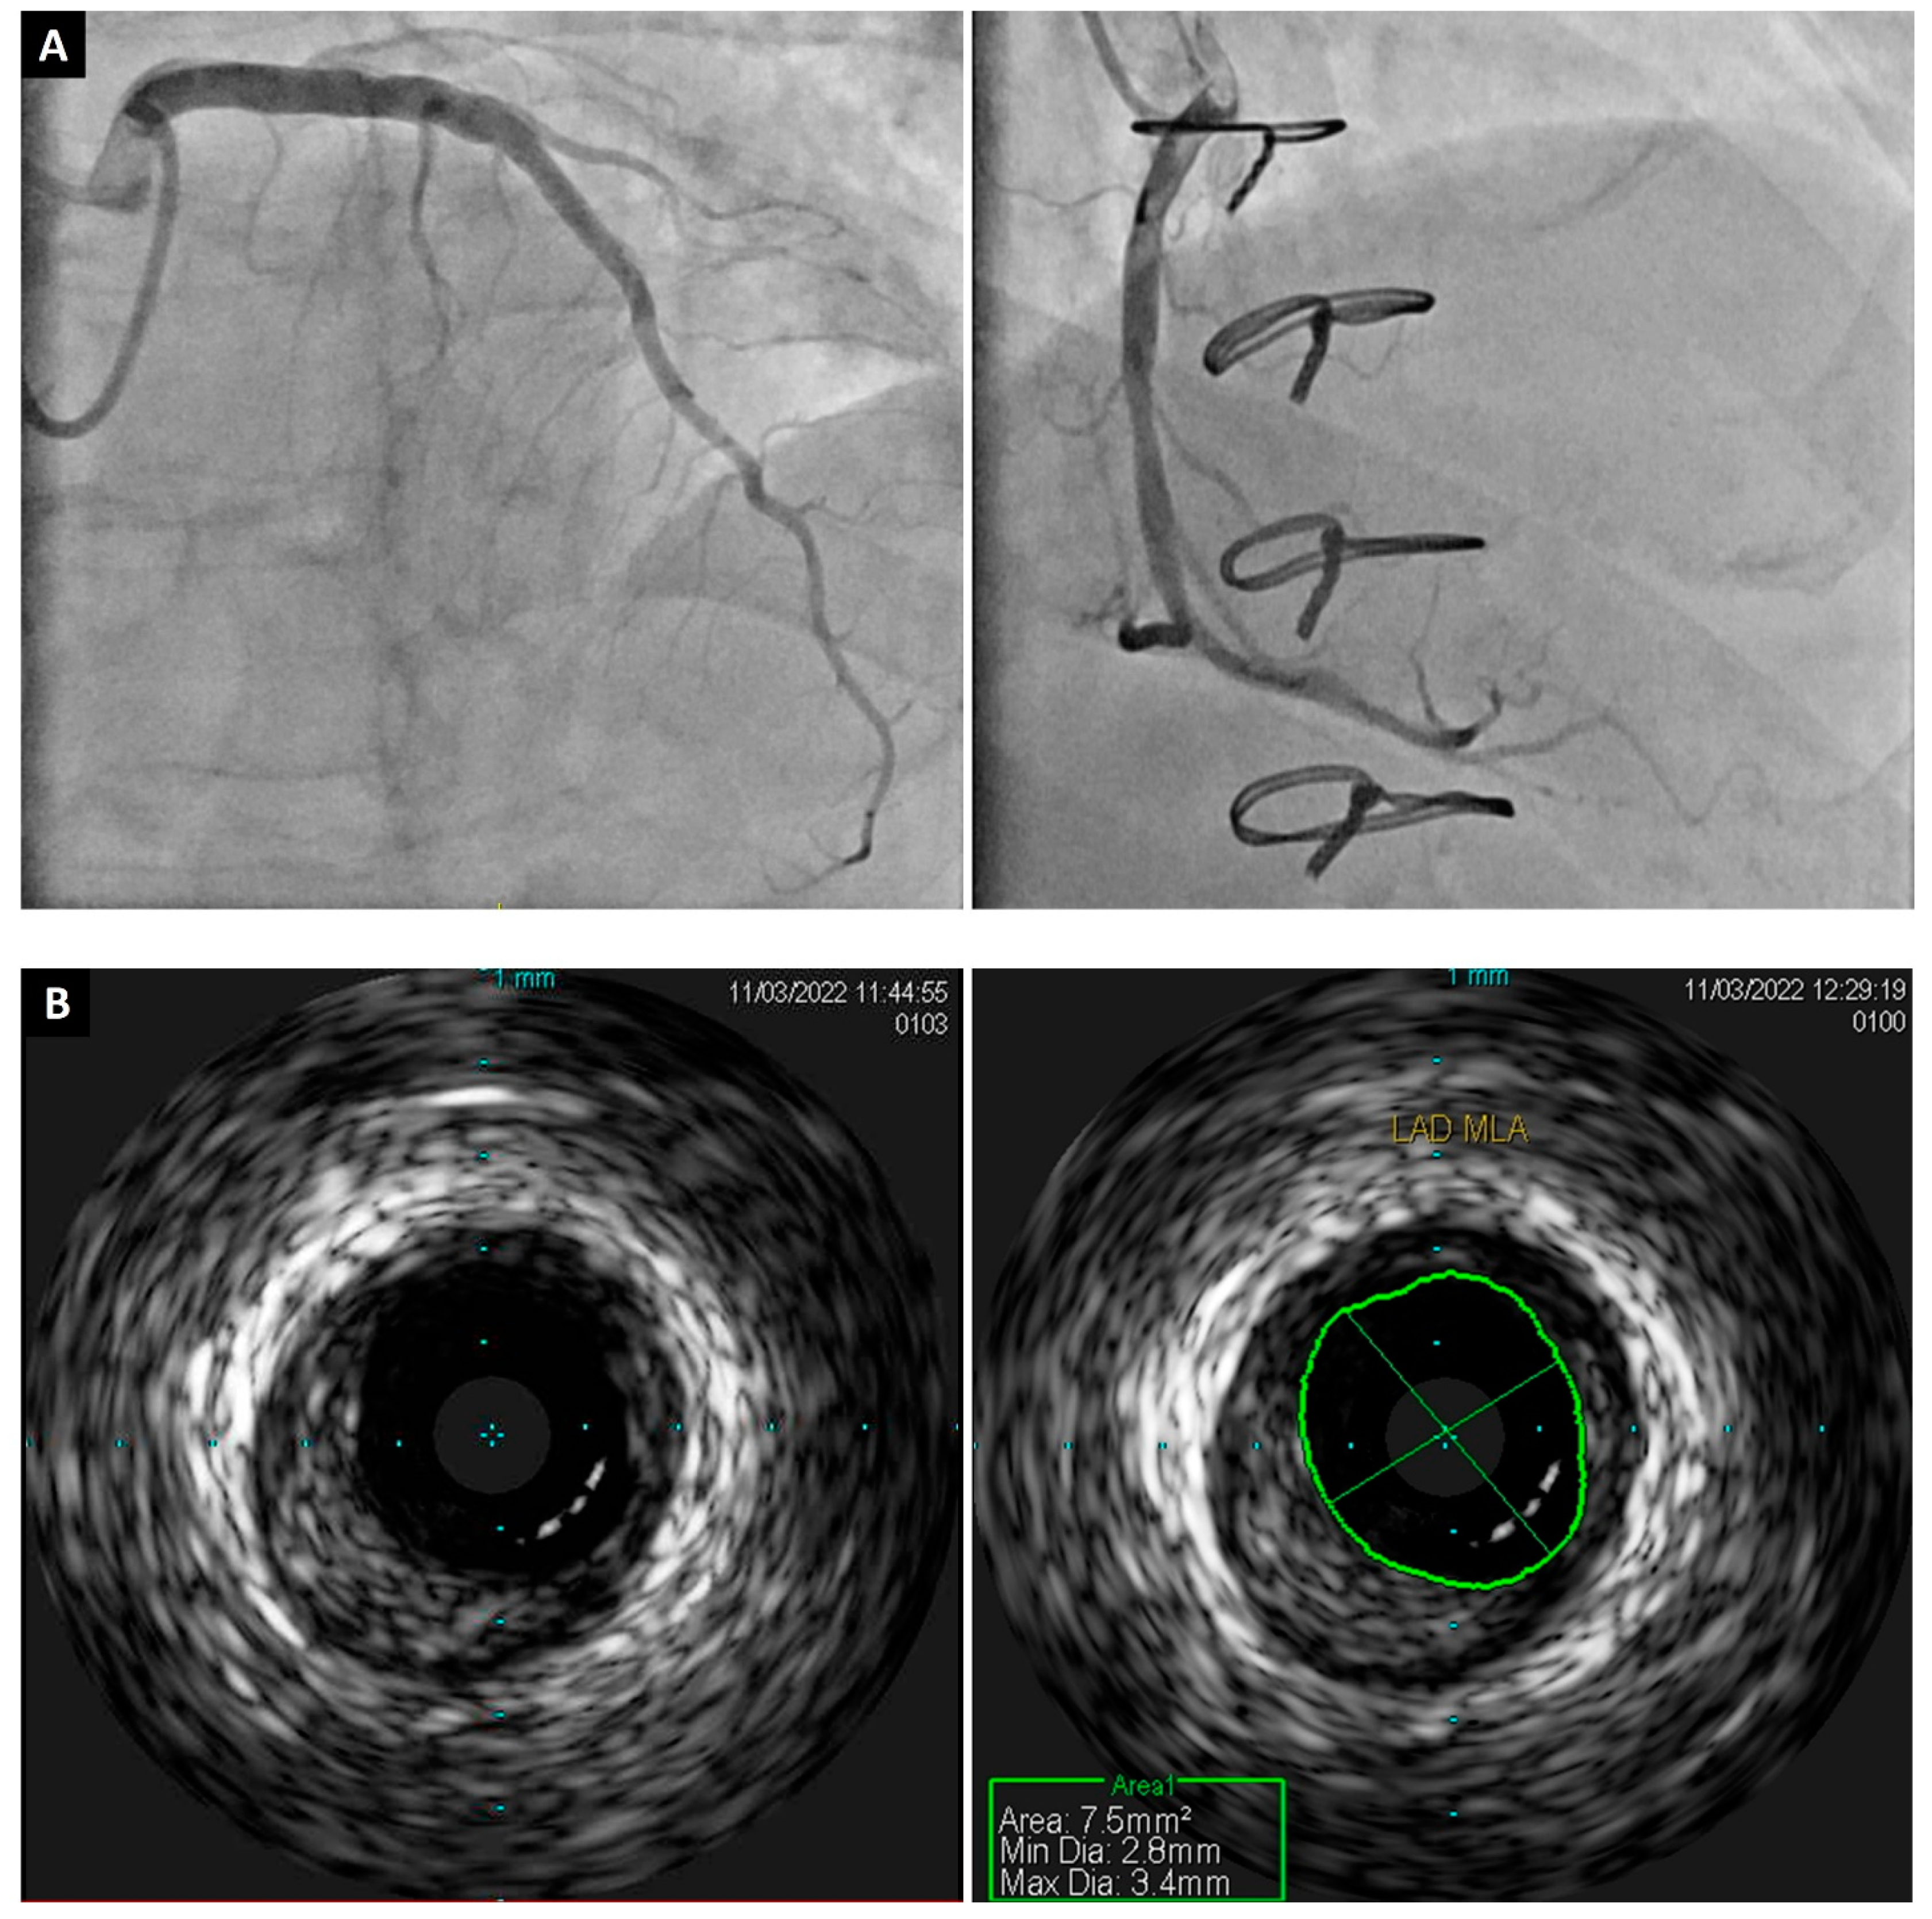

Typically performed during ICA four to six weeks after HTx and again at the one-year mark, IVUS is recognized for its sensitivity in assessing the anatomy of epicardial coronary arteries, including the thickness of intimal and adventitial walls (Figure 2) [23]. The use of IVUS to screen for CAV has increased significantly over the past 20 years because it allows for the earlier detection of intimal thickening before this process may be apparent on ICA [15]. Multiple studies have demonstrated the prognostic impact of the IVUS-based parameter, maximal intimal thickness (MIT), in the early detection of CAV [24]. In these studies, an MIT greater than 0.5 mm was associated with higher rates of mortality, cardiac events, and revascularization four years after HTx [25]. Although combining IVUS with ICA is the current standard for the early detection of CAV, it has its own limitations of an increased risk of complications during angiography and an increased time and cost of the procedure, along with limited vessel coverage [24].

Figure 2.

A 62-year-old male patient who developed CAV 10 years after heart transplant. (A) Conventional ICA showing no significant stenosis; middle left anterior descending artery is 10% obstructed by diffuse disease and middle right coronary artery is 20% obstructed by diffuse disease. (B) IVUS was performed in mid left anterior descending artery and confirmed the presence of significant atherosclerosis. CAV, cardiac allograft vasculopathy; ICA, invasive coronary angiography; IVUS, intravascular ultrasound.